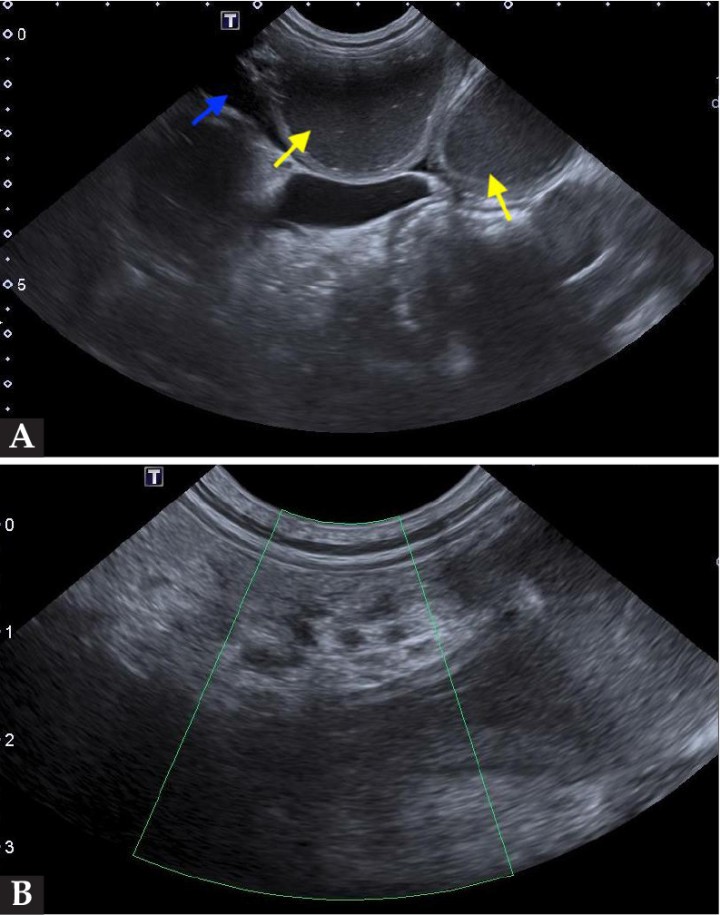

Se realizó una ecografía abdominal, en la que se visualizaron todas las asas intestinales muy dilatadas (flechas amarillas; Fig. 3A). Los vasos mesentéricos se encontraban distendidos, apreciándose cambios en la dirección de su trayectoria de manera abrupta. Dichos vasos carecían de flujo sanguíneo al emplear el modo Doppler color, siendo este el hallazgo más significativo (Fig. 3B).

<p>Imágenes ecográficas de la cavidad abdominal. (<strong>A</strong>) Se puede observar las asas intestinales dilatadas con contenido líquido en su interior (flechas amarillas) y líquido libre abdominal (flecha azul). (<strong>B</strong>) Se muestra la ausencia de señal Doppler color en los vasos mesentéricos.</p>

Imágenes ecográficas de la cavidad abdominal. (A) Se puede observar las asas intestinales dilatadas con contenido líquido en su interior (flechas amarillas) y líquido libre abdominal (flecha azul). (B) Se muestra la ausencia de señal Doppler color en los vasos mesentéricos.

En el examen ecográfico de la cavidad abdominal se suele identificar marcada distensión intestinal, con acumulación de contenido líquido y gaseoso intraluminal, y un peristaltismo muy reducido o incluso ausente. Lo más destacable es que al emplear el modo Doppler color no se detecta flujo sanguíneo en los vasos que irrigan los tramos intestinales afectados. En ocasiones, se puede observar una moderada cantidad de líquido libre y el omento hiperecoico y reactivo.[ Dennis, R, Kirberger, RM, Barr, F, Wrigley, RH: Gastrointestinal tract. En Dennis, R, Kirberger, RM, Barr, F, Wrigley, RH (ed): Handbook of Small Animal Radiology and Ultrasound, Croydon (UK), Elsevier, 2010; 267-295. , Rautala E, Björkenheim P, Laitinen M: Radiographic and ultrasonographic findings in three surgically confirmed cases of small intestinal ischemia related to mesenteric volvulus or intestinal torsión in dogs. Open J Vet Med 2017; 7: 99-110. ]